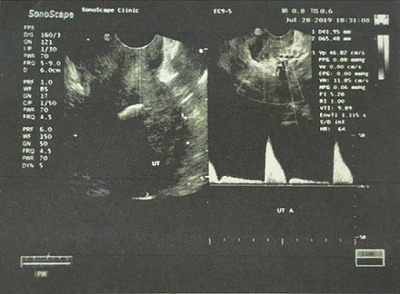

Case presentation: We present two cases of OM presented to the infertility clinic and discuss their similarities and discrepancies in presentation and risk factors. A transvaginal ultrasound raises suspicion about the diagnosis of OM with a hyperechoic mass and post-acoustic shadowing. An office hysteroscopy showed white, mesh-like bony sheets. Both cases underwent operative hysteroscopy to address surgical challenges, and the two cases were followed postoperatively for one year.

Conclusion: OM should be considered in the evaluation of infertility despite its rarity, especially with hyperechoic lesions and acoustic shadowing on ultrasound examination. Hysteroscopy is the gold standard for diagnosis and therapeutic approaches. A complete understanding of the reasons that trigger its growth is crucial. To rule out other differential diagnosis, a holistic evaluation of the patient's history, imaging, and histopathological examination is needed.